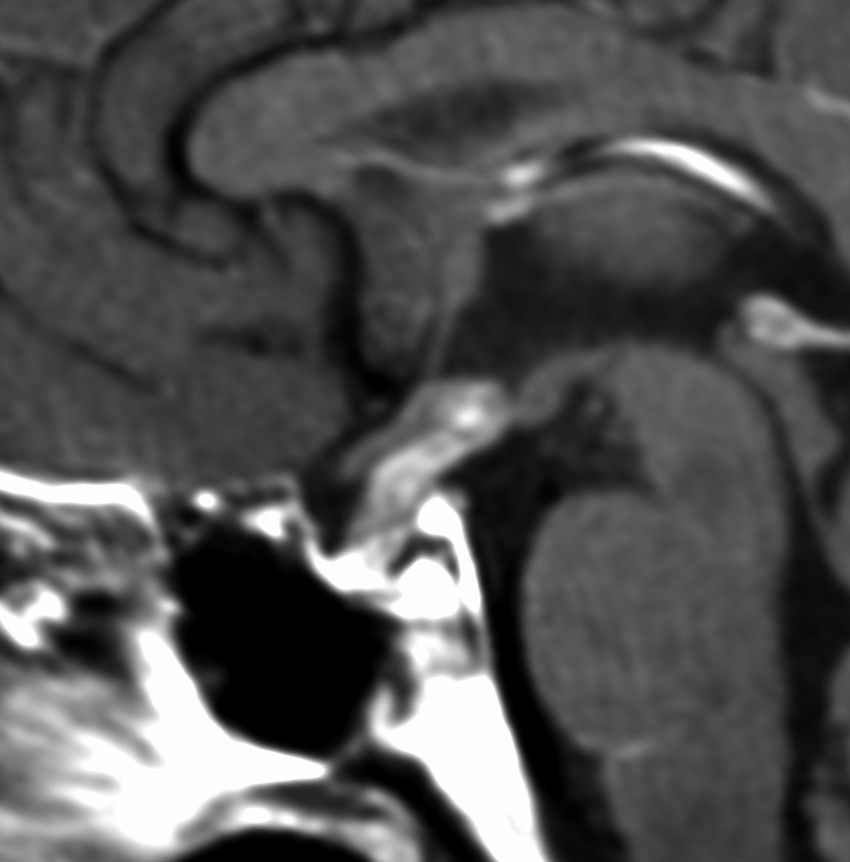

血清HCGが2.1mIU/ml,尿崩症で発症した思春期男児です。石灰化はありませんし,脂肪組織なども混在しません。生検術をしなくてもgerminomaと診断できます。でも簡単なので,経鼻的な生検術を行った方がいいです。

この例は18歳,HCG 0.1mIU/ml,尿崩症で発症しました。神経下垂体ジャーミノーマなので,下垂体前葉のみが残って後葉から視床下部が腫瘍化しています。よくよく見ると松果体にもごく小さな腫瘍があります。右のCISS画像で松果体の腫瘍化が明瞭です。

経鼻生検術で下垂体後葉部分がgerminomaということを確認してからICE (IFO/CDDP/VP-16)を1コース加えて3週間後の画像です。腫瘍は灰白隆起の部分を残してほぼ消失しています。松果体部の腫瘍も消えています。典型的なgerminomaの化学療法反応性を示しています。下垂体前葉機能は正常,尿崩症も少し良くなりました。